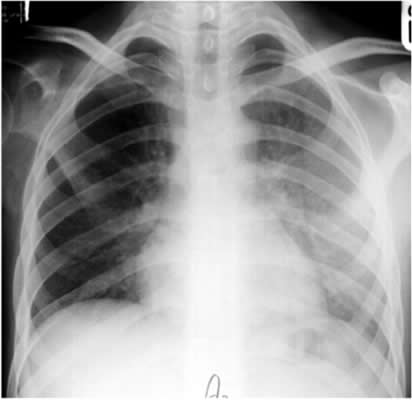

Answer: Yes. You must make sure that the film has been taken in full inspiration, as shown in this image.

At least six ribs should be visible anteriorly and 10 ribs posteriorly.

An expiratory film can look very abnormal.

These two films were taken seconds apart.